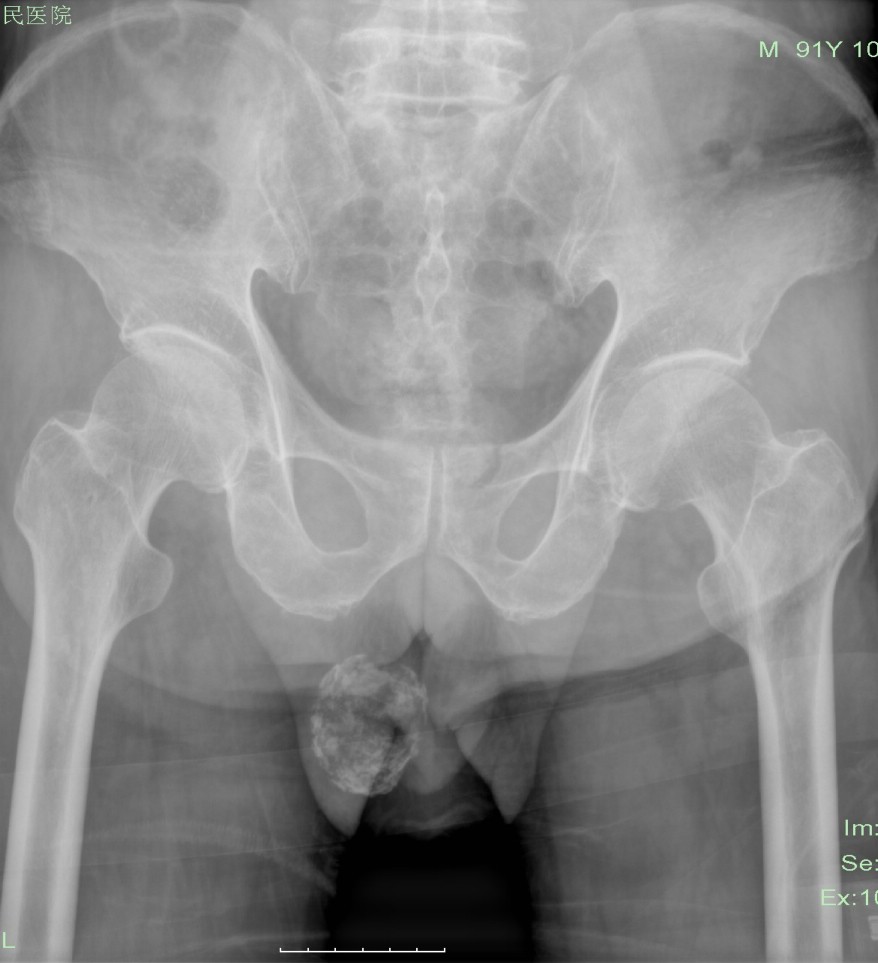

男性,55岁,请大家看看,这个片位于耻骨联合处是什么?

病史:排尿困难10年余,加重3天

迷漫性前列腺钙化

考虑:弥漫性前列腺点状钙化!

照个侧位像,排除一下膀胱结石 ,还是前列腺钙化可能大

前列腺钙化,ct扫描更准确些

支持 弥漫性前列腺钙化伴尿潴留。

弥漫性前列腺钙化或结石致尿潴留。

从位置来看应该能排除膀胱结石,支持弥漫性前列腺钙化。 真是少见的好片子,学习了!